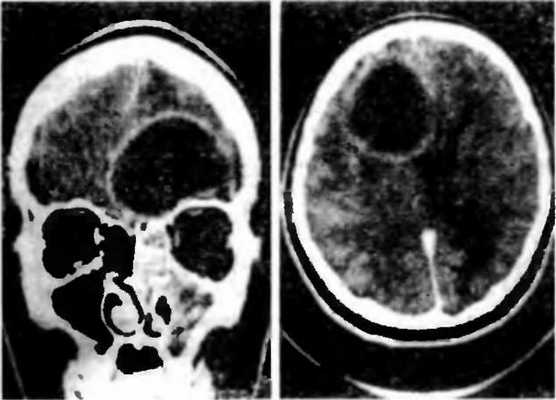

Для того чтобы провести точную диагностику места расположения абсцесса мозга и мозжечка, проводят компьютерную и магнитно-резонансную томографию головного мозга. При проведении компьютерной томографии выявляется тонкая, гладкая стенка абсцесса, которая имеет правильные контуры. Магнитно-резонансная томография позволяет также определить капсулу абсцесса. Если нет возможности провести вышеперечисленные виды исследования, можно провести пневмоэнцефалографию или радиоизотопную сцинтиграфию головного мозга.

При диагностике абсцесса головного мозга большое значение имеет проведение эхоэнцефалографии (ультразвуковая диагностика). Она позволяет определить наличие в полости черепа объемных процессов - кист, абсцессов и т.д. Эффективно проведение электроэнцефалографии (исследование электрической активности мозга), радиоизотопная сцинтиграфия (исследование с использованием радиоактивных изотопов), компьютерная и резонансно-магнитная томография.

Точность диагностирования с помощью КТ головного мозга зависит от стадии формирования абсцесса. На ранних стадиях заболевания диагностика затруднена. На этапе раннего энцефалита (1-3 сутки) КТ определяет зону сниженной плотности неправильной формы. Введенное контрастное вещество накапливается неравномерно, преимущественно периферических отделах очага, реже в центре.

На более поздних этапах энцефалита контуры очага приобретают ровные округлые очертания. Контрастное вещество распределяется равномерно, по всей периферии очага; плотность центральной зоны очага при этом не меняется. Однако на повторной КТ (через 30-40 минут) определяется диффузия контраста в центр капсулы, а также наличие его и в периферической зоне, что не характерно для злокачественных новообразований.

Инкапсулированный абсцесс мозга на КТ имеет вид округлого объемного образования с четкими ровными контурами повышенной плотности (фиброзная капсула). В центре капсулы зона пониженной плотности (гной), по периферии видна зона отека. Введенное контрастное вещество накапливается в виде кольца (по контуру фиброзной капсулы) с небольшой прилежащей зоной глиоза.

На повторной КТ (через 30-40 минут) контрастное вещество не определяется. При исследовании результатов компьютерной томографии следует учесть, что противовоспалительные препараты (глюкокортикостероиды, салицилаты) в значительной степени влияют на скопление контраста в энцефалитическом очаге.